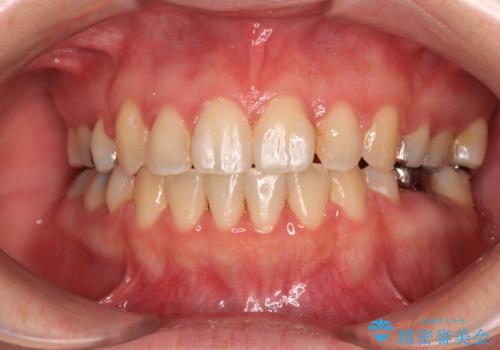

口元の突出感とデコボコがあり、上下左右の小臼歯4本を抜歯して矯正治療を行う方針としました。(右上は欠損のため計3本抜歯)

イレギュラーな大臼歯抜歯矯正であったため、治療期間の長期化が想定されましたが、何とか3年ちょうどで終えることができました。

今後は目立っている銀歯を中心にセラミッククラウンなどへ交換していく予定です。